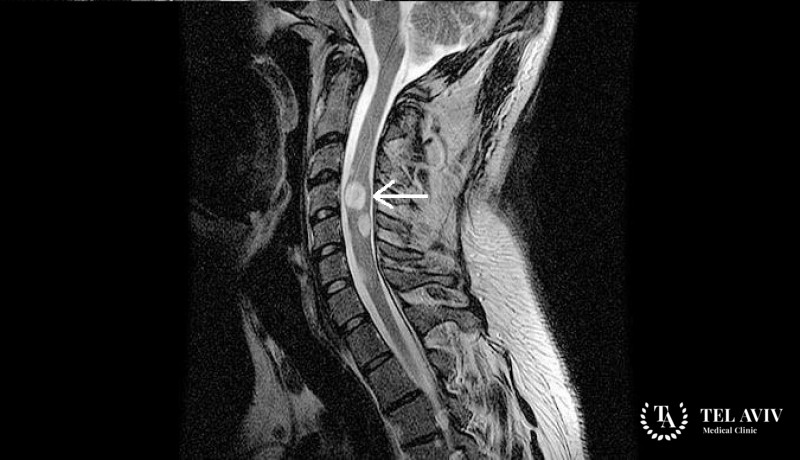

- КТ или МРТ;

- Биопсия для определения раковых клеток.